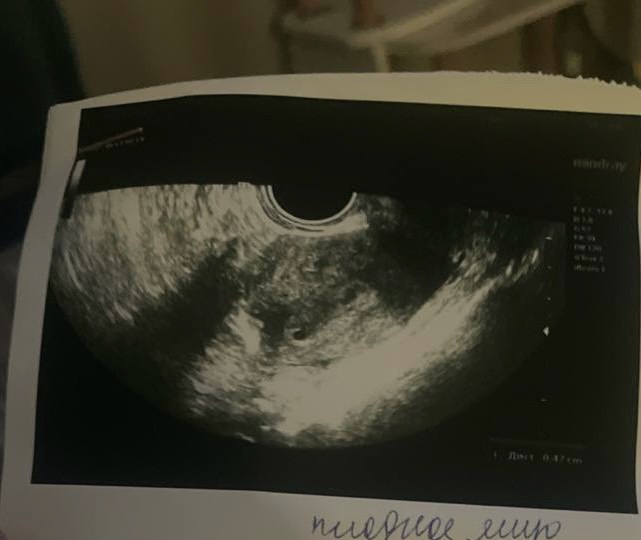

Всем привет. Девочки , у меня глюк или тут 2 плодных яйца ?

Может быть 2 яйца, а может яйцо и гематома. Чуть позже ясно станет

Сказала одно плодное яйцо и 2 желтых тела в одном яичнике

Я не уверена в ее компетенции , ходила чтобы исключить внематочную

Да вроде одно